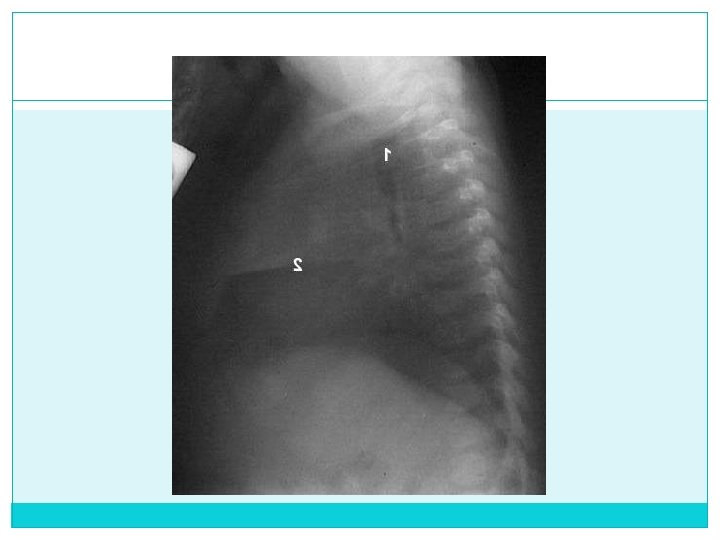

d) Definición Buena: No movimiento del paciente e) Centrado: Frontal: Extremos mediales clavícula equidistantes a línea media (apófisis espinosas) Lateral: Arco Costal posterior de un hemitórax se distancia de su contralateral max. 1 cm